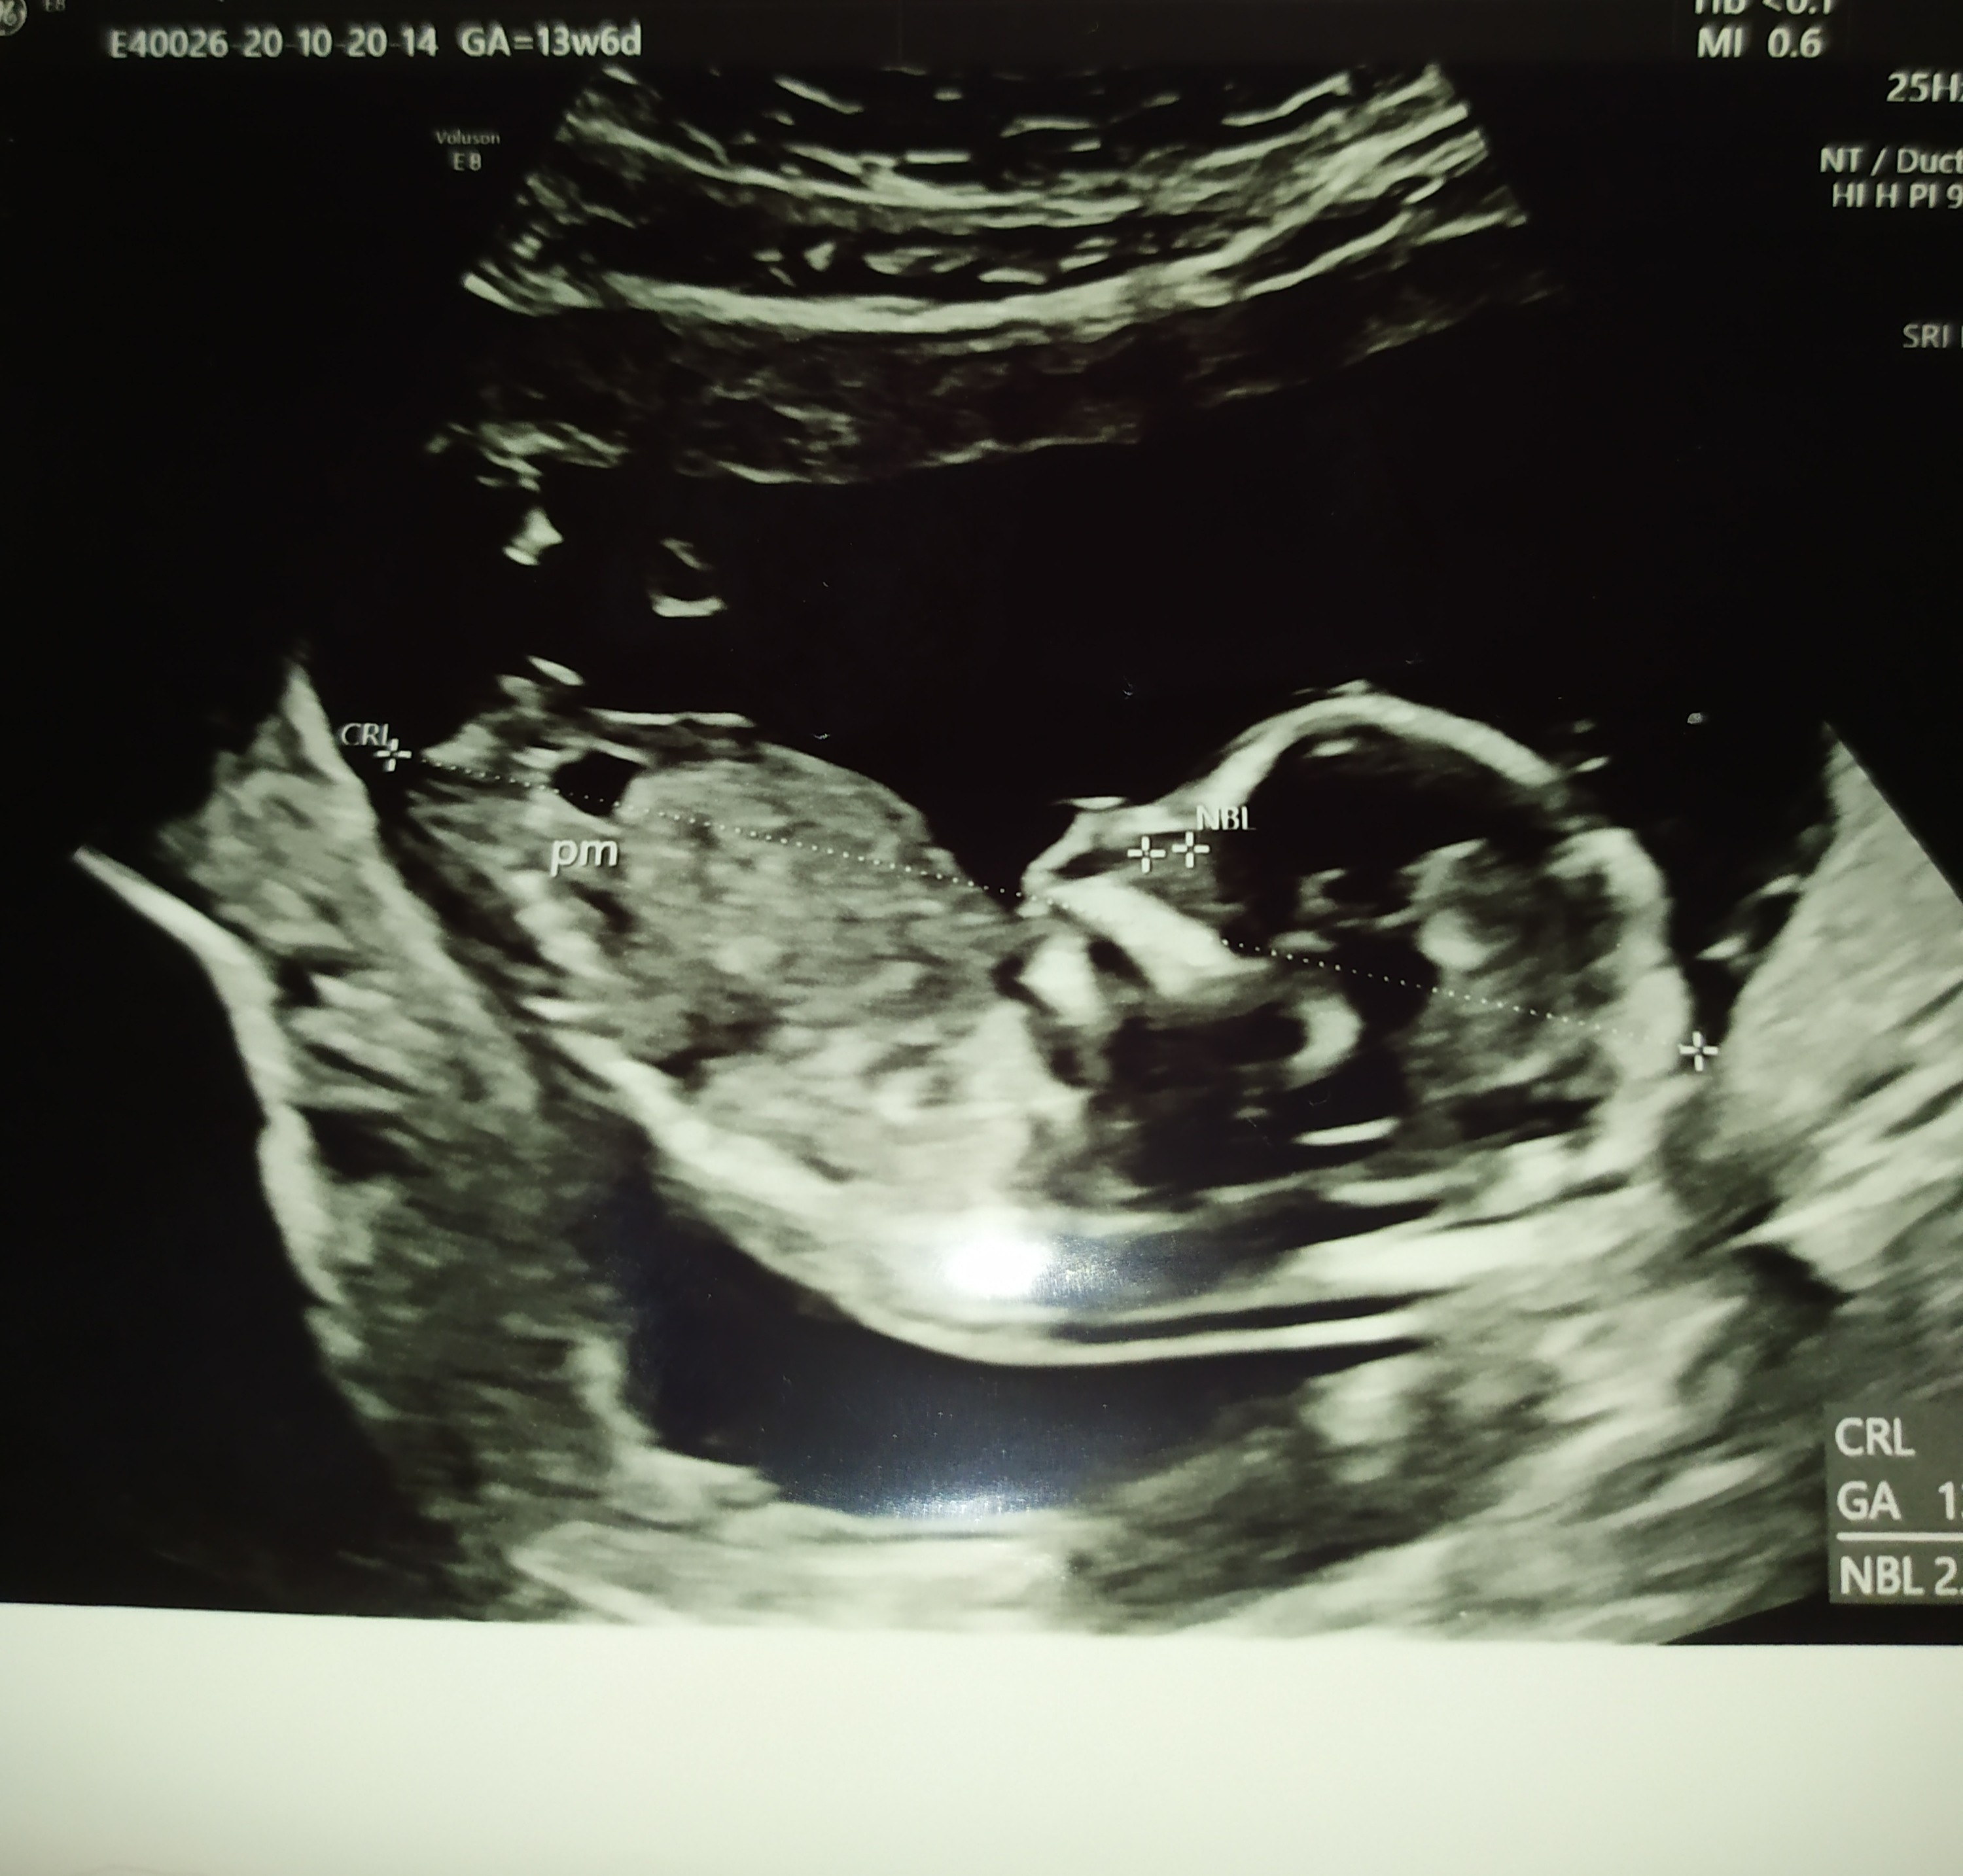

Z przyjemniejszych rzeczy dzidzia coraz bardziej daje znać o sobie

Jak mąż wczoraj mnie drapal pod pepkiem to zaraz się odzywała